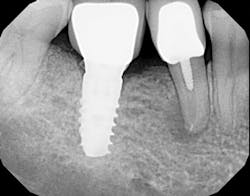

The most critical aspect of any implant system is the interface between the implant fixture and its surrounding bone (figures 1-5). Integration between the fixture and its surrounding bone is the foundation of modern implant dentistry. There is little we can do to modulate bone healing, but we can modify the implant fixture itself.

Figures 1-5: Figures 1 through 4 illustrate, respectively, a seven-year follow-up visit and a three-year follow-up visit of two different implant systems. Implant No. 22 (figure 5) shows peri-implant radiolucency following functional loading, indicating fibroencapsulation and loss of integration into bone, necessitating removal.